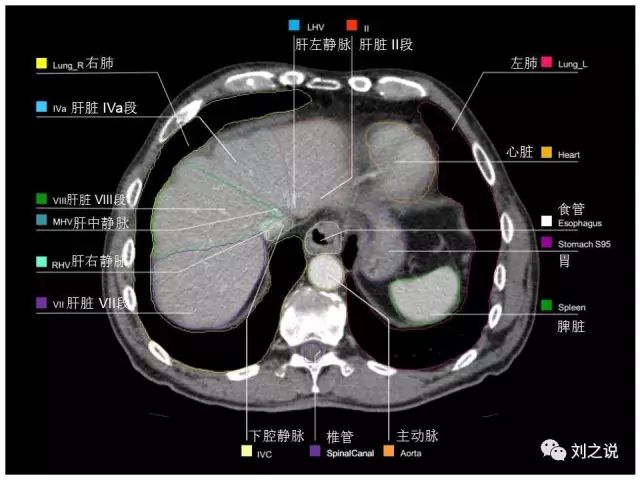

参考RTOG共识和3D-body解剖。

来源:刘之说